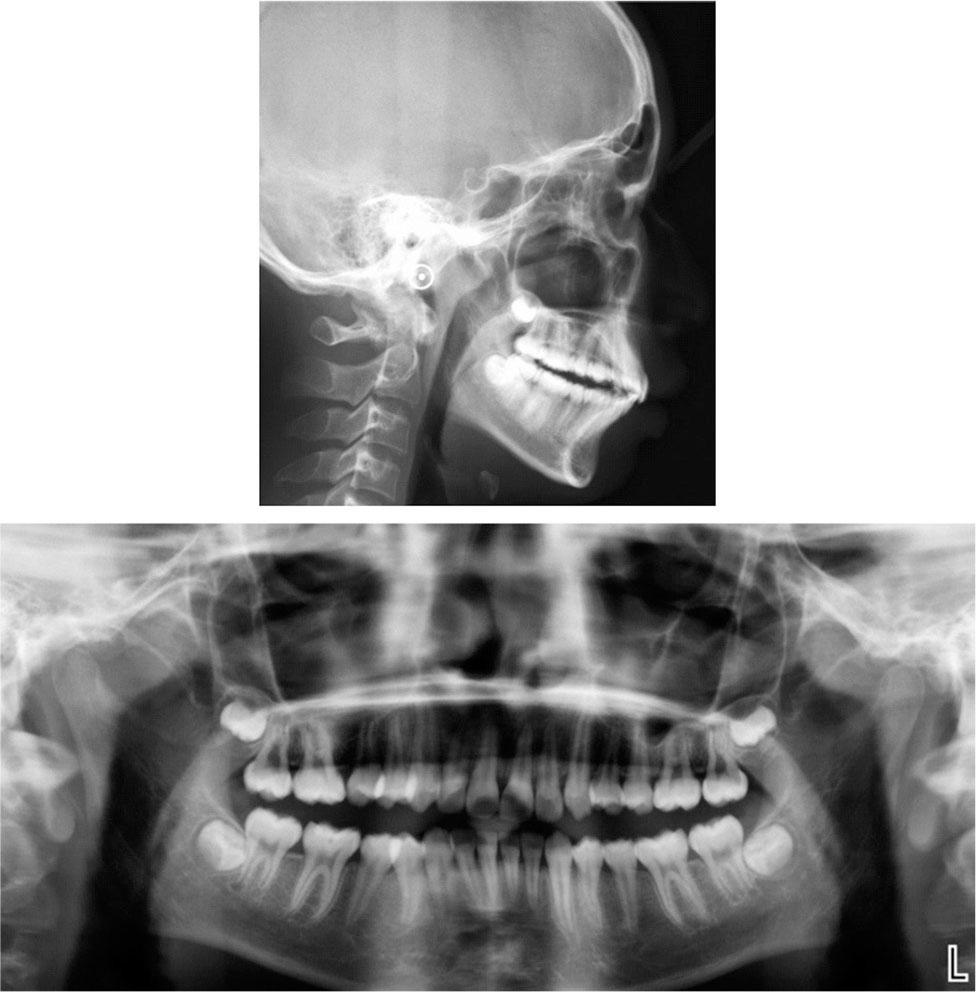

Cephalometric measurements (T1 Pretreatment; T2 12 months after Twin-block treatment; T3 36 months after fixed orthodontic treatment)

| Measurement | Norm | T1 | T2 | T3 |

|---|---|---|---|---|

| SNA(°) | 83.0 | 87.3 | 86.8 | 86.1 |

| SNB(°) | 80.0 | 77.9 | 79.6 | 81.6 |

| ANB(°) | 3.0 | 9.4 | 7.2 | 4.5 |

| NP-FH(°) | 85.0 | 81.5 | 84.5 | 84.4 |

| NA-PA(°) | 6.0 | 19.8 | 16.5 | 10.0 |

| U1-SN(°) | 105.0 | 108.8 | 101.3 | 107.9 |

| U1-NA(°) | 22.0 | 21.6 | 14.5 | 21.9 |

| L1-NB(°) | 30.0 | 37.3 | 41.4 | 25.6 |

| IMPA(°) | 88.0 | 111.0 | 113.2 | 98.7 |

| FMIA(°) | 67.0 | 44.0 | 43.1 | 59.0 |

| FMA(°) | 25.0 | 25.0 | 23.7 | 22.3 |

| Y-axis angle (°) | 65.8 | 65.8 | 64.2 | 64.0 |

| Z-angle(°) | 75.0 | 52.8 | 59.7 | 65.3 |

| Po-Go(mm) | – | 6.9 | 7.2 | 7.3 |

| Gn-Co(mm) | – | 10.2 | 10.8 | 11.1 |